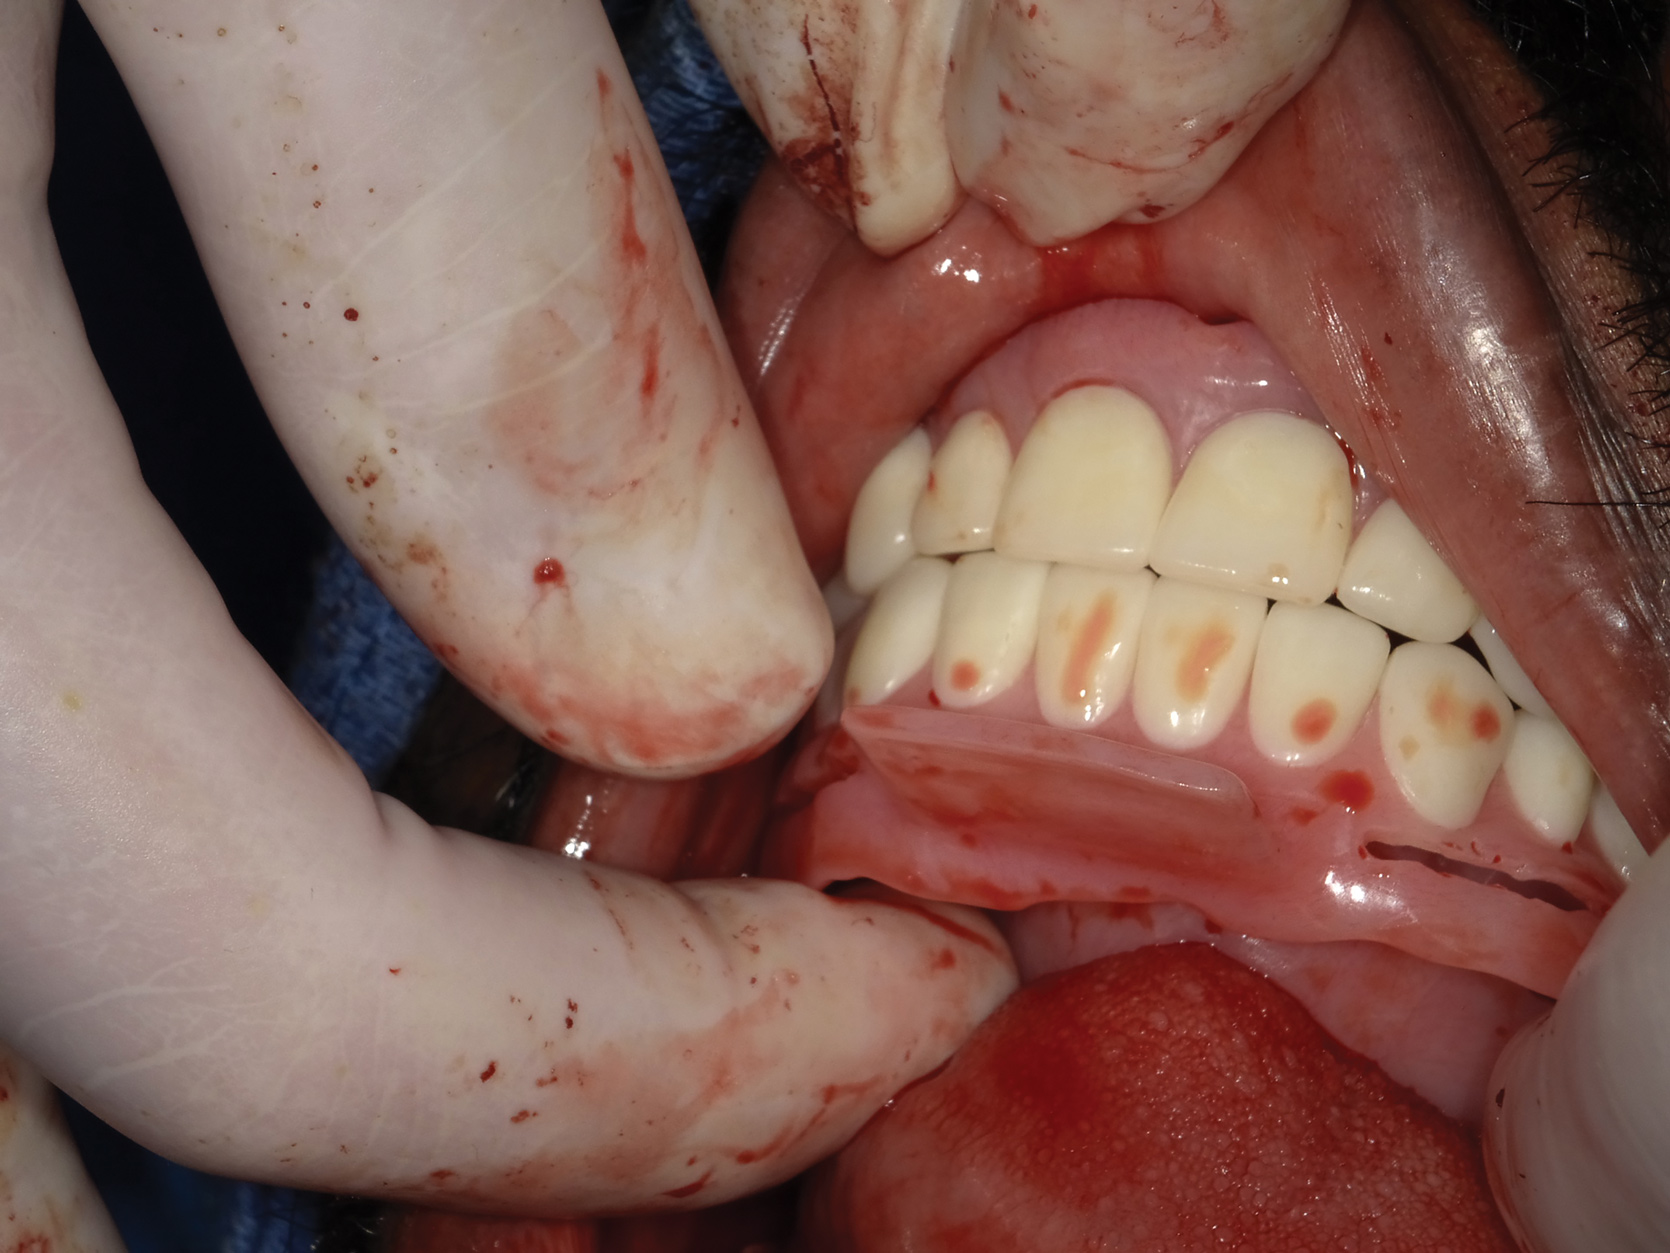

Figure 14: The pre-operative condition of the patient is shown in this front view.

Figure 14